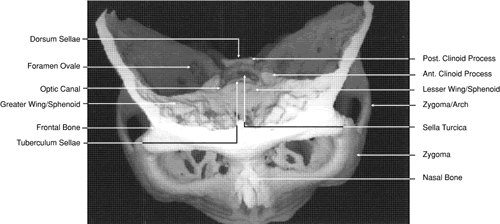

Fig. 29. A. Axial computed tomography soft tissue image at the level of the base of skull. B. Axial computed tomography bone window image at the level of the base of skull.